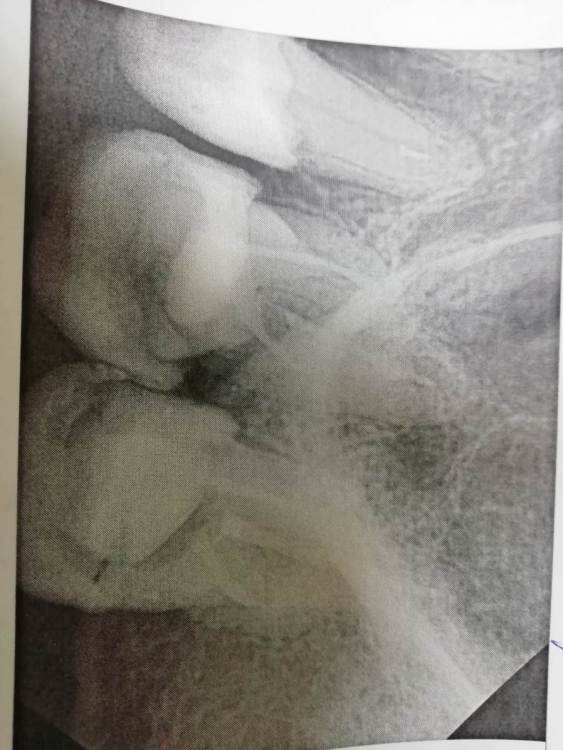

laz2000 Опубликовано 23 марта, 2021 Поделиться Опубликовано 23 марта, 2021 Занялся лечением зубов. 25 зуб мне должны были запломбировать каналы, поставить штифт и поставить световую пломбу. 26 и 27 зуб — пока только пролечены и запломбированы каналы. Несколько вопросов: 1. насколько качественно запломбированы каналы 26 и 27 зуба? (Врач почему то сказал может быть надо будет каналы в 26 зубе уплотнять, но будет думать) 2. 25 зуб — запломбированы ли каналы этого зуба вообще? 3. 25 зуб — установлен ли штифт? Во вложенных файлах снимки этих трех зубов. Ссылка на комментарий

red_butler Опубликовано 24 марта, 2021 Поделиться Опубликовано 24 марта, 2021 качество снимков не позволяет дать полноценные ответы, кроме всего нужен очный осмотр. В зависимости от степени разрушения, или протезировать искусственными коронками, или удалять Ссылка на комментарий

red_butler Опубликовано 26 марта, 2021 Поделиться Опубликовано 26 марта, 2021 2 часа назад, laz2000 сказал: Извините, Скажите пожалуйста Вы уверены, что каналы 25 зуба полностью запломбированы? Вы читали что я сказал что ваши снимки плохие???? Я вижу в канале следы пломбировочного материала. Покажите снимки нормального качества, в идеале срезы Кт, и фото во рту. Пока предположительный прогноз по Впшим зубам- плохой Ссылка на комментарий